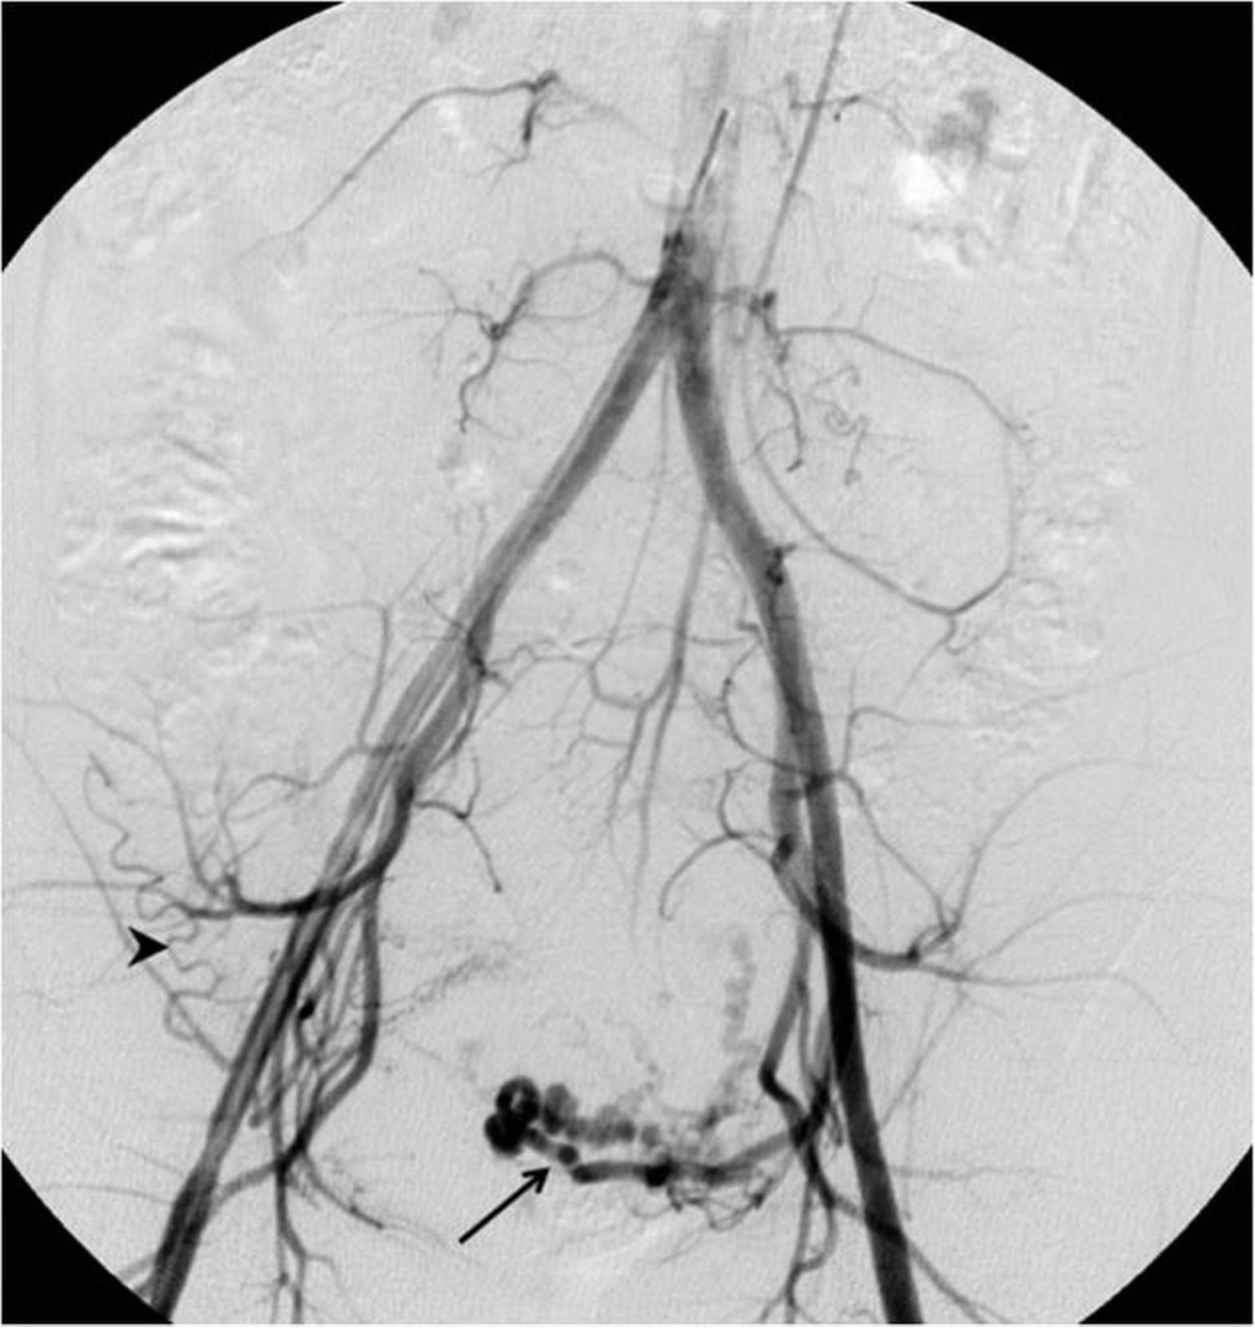

Fig. 2. A

Fig. 2A-C. Pelvic angiogram (A) shows the tortuous and dilated left uterine artery (arrow) and atrophy of the right uterine artery. An aberrant ovarian collateral (arrowhead) originates from the right external iliac artery. Selective right external iliac angiogram (B) reveals the aberrant ovarian collateral (thin arrow), right inferior epigastric(thick arrow), and right round ligament(arrowhead) arteries. Selective aberrant ovarian collateral angiogram (C) demonstrates that the collateral supplies blood flow to the right half of the uterus as well as the right ovary (arrow).